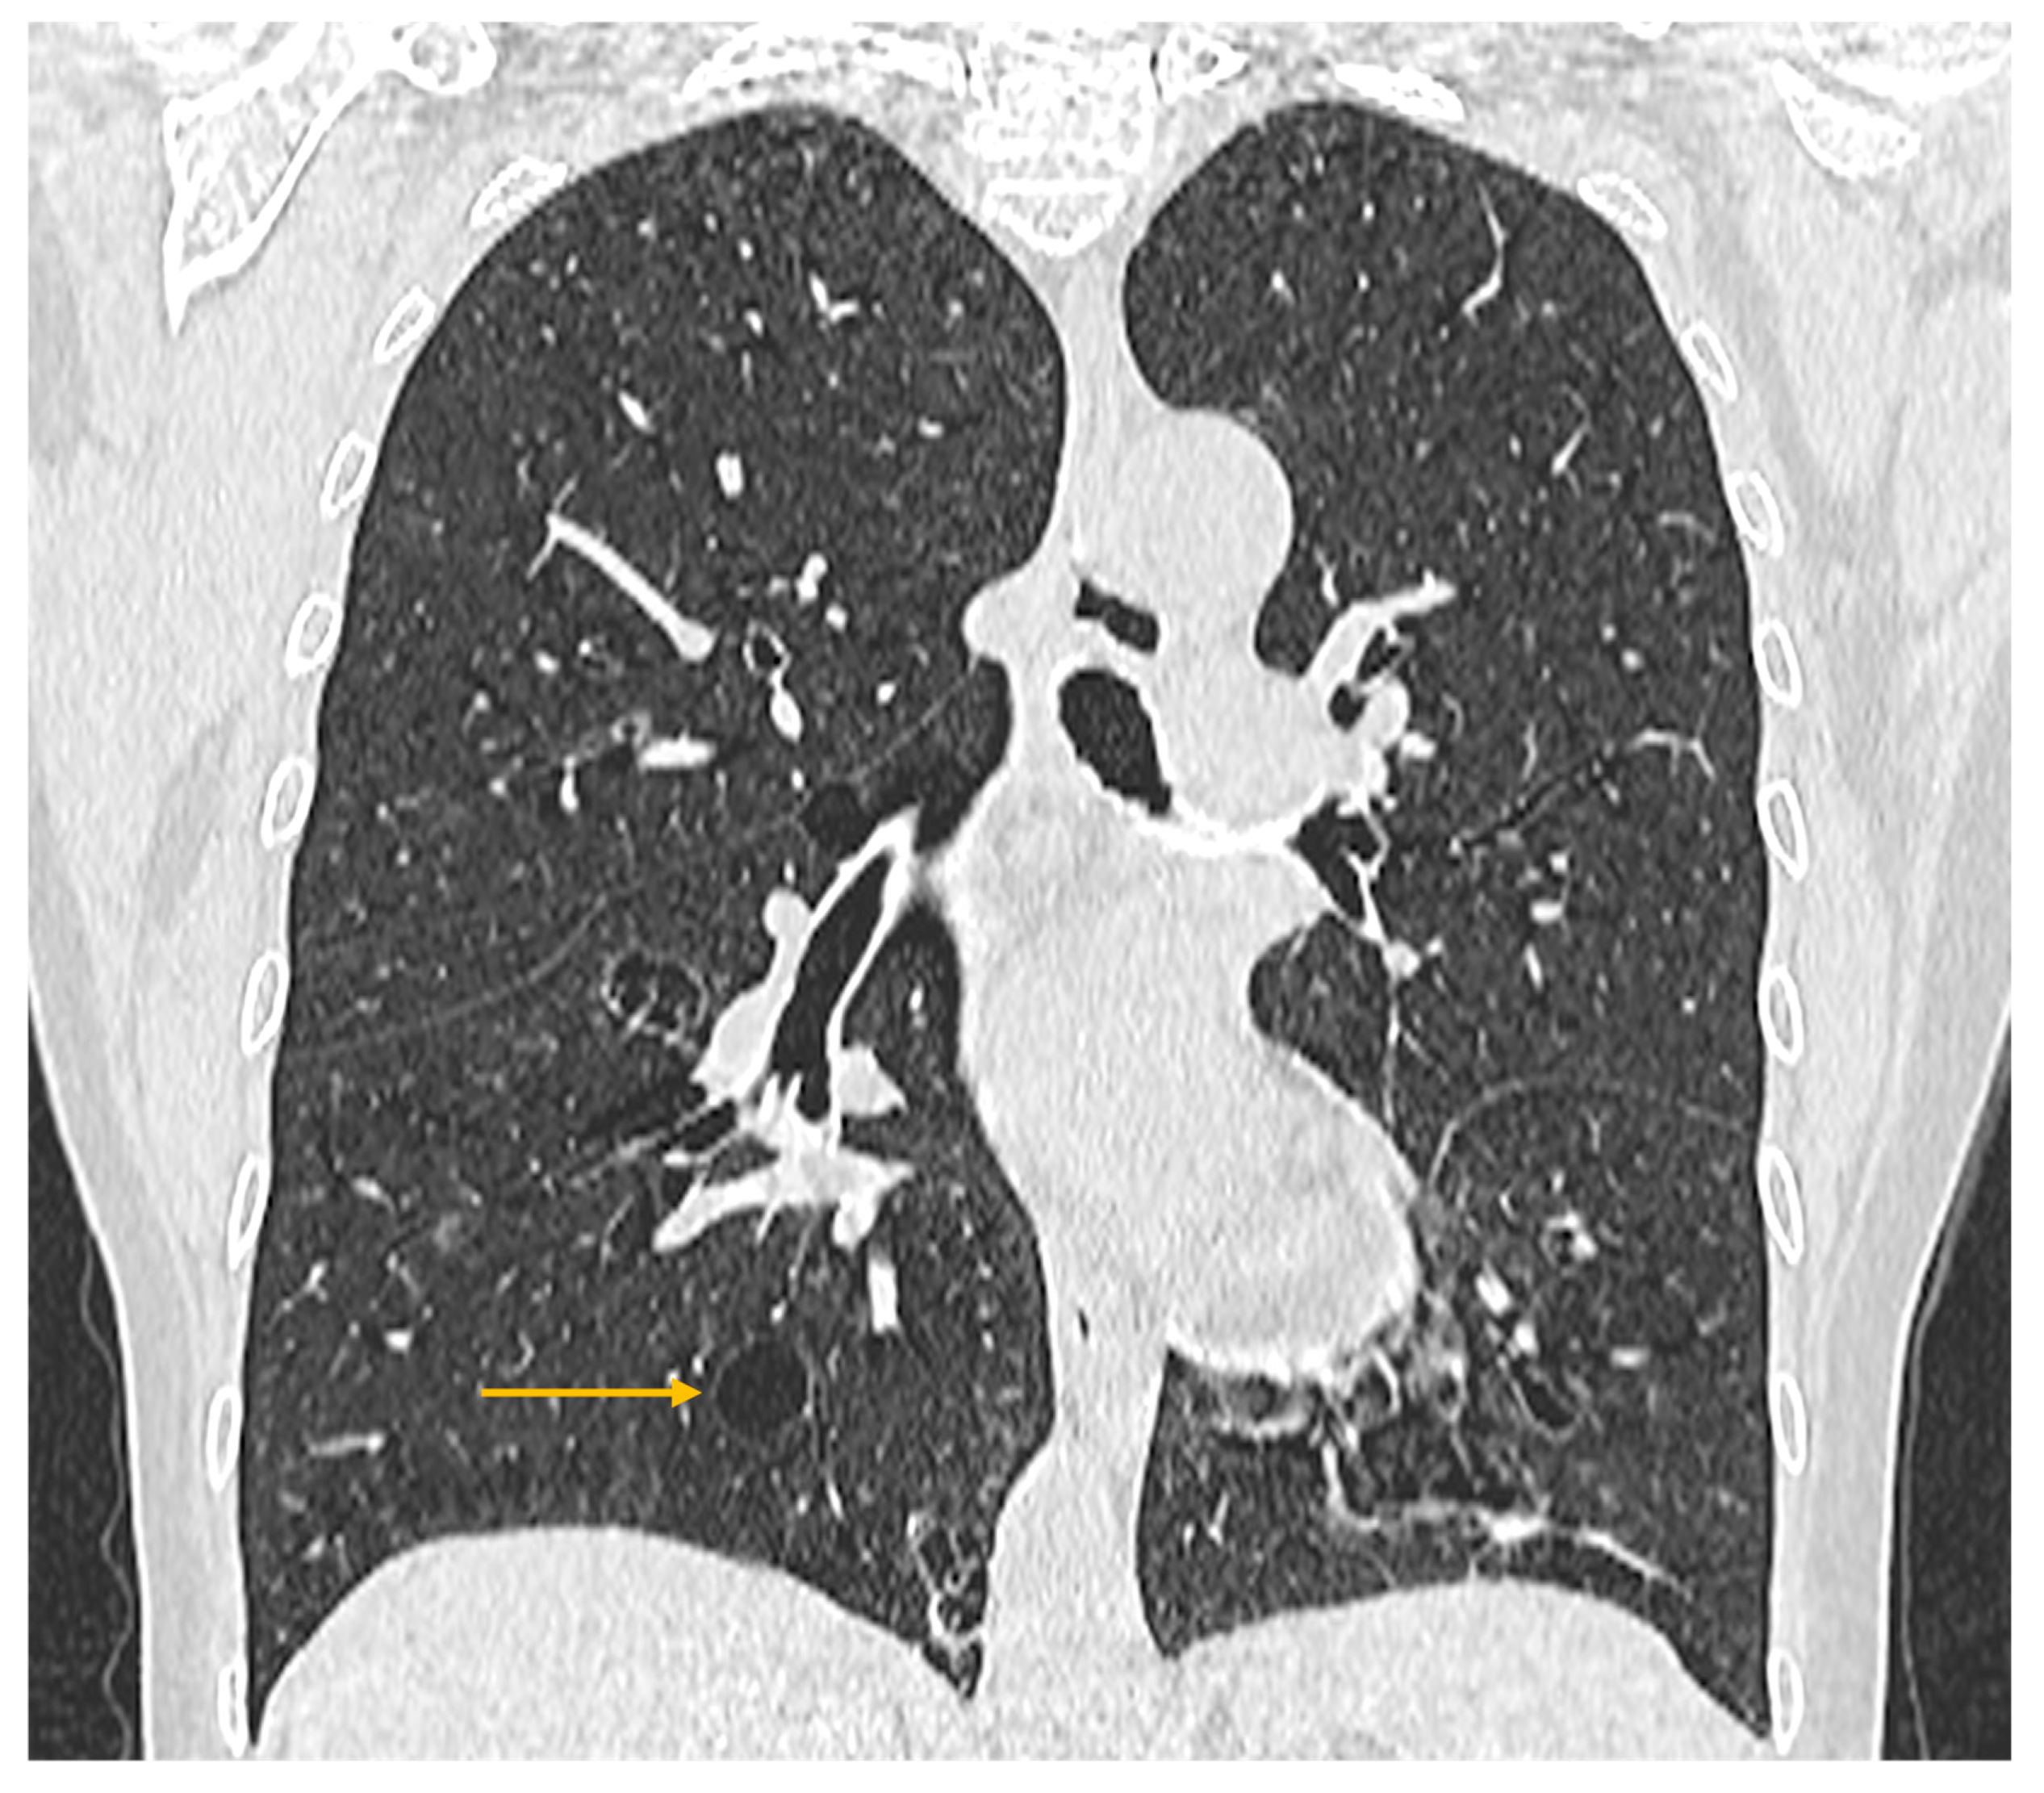

Pulmonary involvement in patients with Sjögren’s syndrome manifests with symptoms such as persistent cough and dyspnea, associated with abnormal findings on diagnostic tests (pulmonary function tests and high-resolution computed tomography—HRCT) [37]. Pulmonary manifestations result from diffuse interstitial pathologies that develop in these patients, the most frequent histologic subtype being non-specific interstitial pneumonia (NSIP) [47], followed by usual interstitial pneumonia (UIP), lymphoid interstitial pneumonia (LIP), and organizing pneumonia (OP) [24]. The prevalence of interstitial lung disease among patients with Sjögren’s syndrome is 23% [24].

High-resolution computed tomography represents the gold standard for evaluating pulmonary changes in diffuse interstitial lung diseases [48]. This imaging technique has a sensitivity of 100%, specificity of 82%, positive predictive value of 97%, and negative predictive value of 100% for the diagnosis of diffuse interstitial disease [49]. The imaging features vary according to the histologic subtype of involvement (Figure 3, Figure 4 and Figure 5) [50].

Figure 5. High-resolution computed tomography (HRCT) of the chest in lymphocytic interstitial pneumonia (LIP). Coronal HRCT image demonstrates thin-walled pulmonary cysts (arrow), a characteristic imaging feature of LIP.